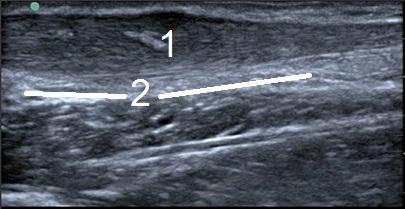

Bild: Fuß und Sprunggelenk, intrasubstantielle Narbenbildung

1. Narbenbildung/Ruptur, ungeordnetes Collagen

2. Schwellung in der Sehne